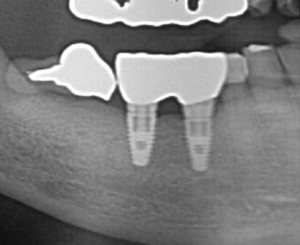

レントゲンがこちらです。

緑の線が元々の既存骨です。骨量は少ないため、上顎洞内部に骨補填剤を充填して赤線部分まで盛り上げました。

その後、時期を分けてインプラントをサージカルガイドを用いて設置していきます。

奥の2つが完成時の歯となります。